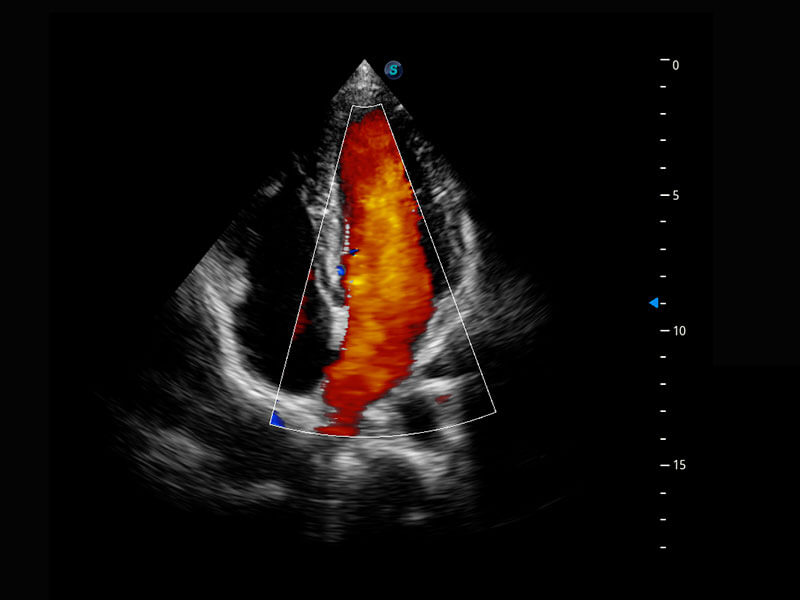

P60搭载一系列胎儿心脏成像技术,实现精细的胎儿心脏评估。

• 四腔心血流